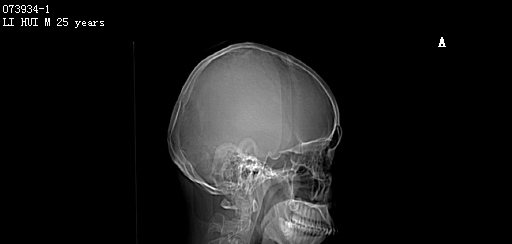

CT51351:M,26y。发现头部肿物10余年。

男,26岁。发现头部肿物10余年。 临床诊断:头部骨肿瘤。 现行头部CT平扫(层厚5mm,层距5mm),图像如下:

考虑双侧顶骨良性骨肿瘤或骨肿瘤样病变(骨纤维异常增殖症?)。

颅骨血管瘤,骨纤,均有可能,建议结合临床病理

嗜酸性肉芽肿可能性大。

右侧顶骨可见膨胀性骨质破坏,破坏区边缘锐利,内见结节高密度影,考虑:颅骨血管瘤可能性大。

啫酸性肉芽肿,颅骨血管瘤,骨纤,均有可能,建议结合临床病理

颅骨血管瘤可能